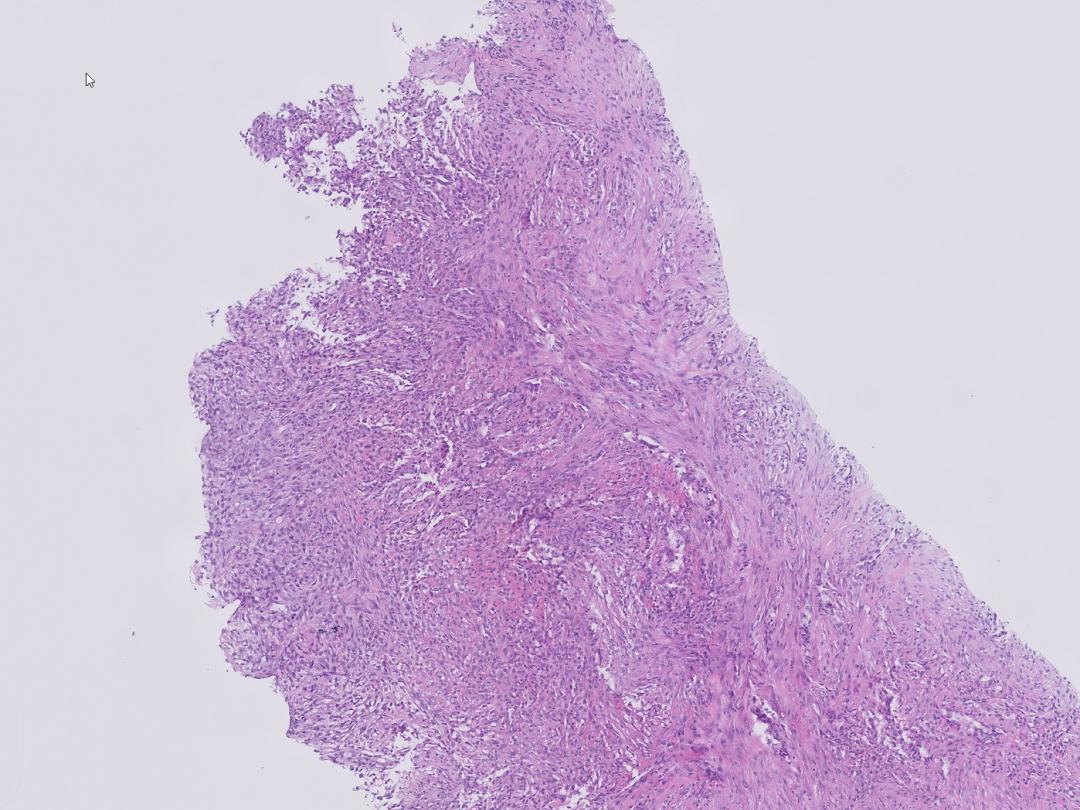

Microscopisch beeld

Een 24-jarige vrouw bij wie eerder een pretibiaal melanoma in situ was geëxcideerd, kwam bij de huisarts met op de onderarm een pijnloze, onderhuidse harde zwelling die in twee weken snel gegroeid was. Echografie liet een subcutane, grillig gevormde, gevasculariseerde massa zien, verdacht voor een maligniteit. Drie dagen later was de zwelling spontaan geslonken. Een nieuwe echo liet een kleinere, ovale, scherp begrensde afwijking zien met inflammatoir aspect. Bij histopathologisch-immunohistochemisch onderzoek van een punctiebiopt zag men een spoelcellige afwijking die bestond uit (myo)fibroblasten met geringe erytrocytextravasatie, passend bij nodulaire fasciitis. Een expectatief beleid werd gevoerd; drie maanden later was de nodus volledig verdwenen.